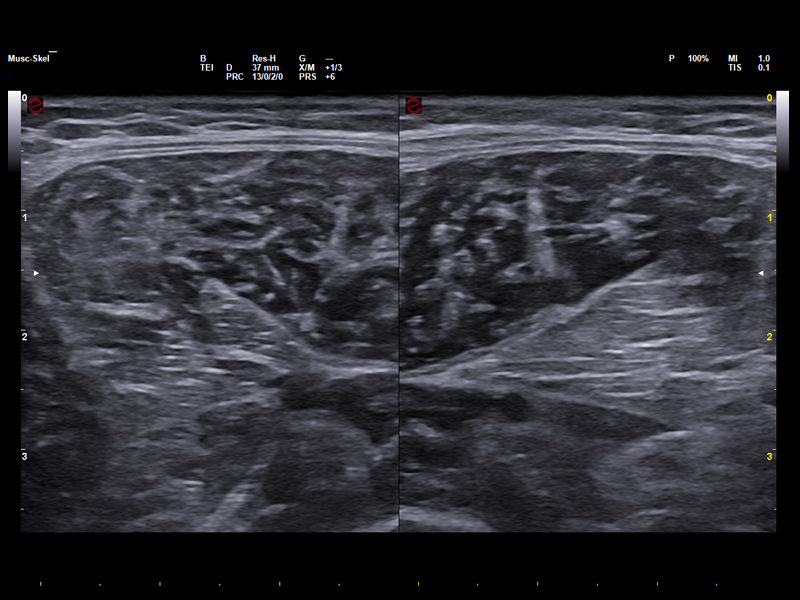

Advanced tissue imaging for athletes

Elastosonography is a highly valuable tool in the field of sports medicine, offering key insights into the mechanical properties of muscles, tendons, and ligaments, thus supporting injury diagnosis, recovery monitoring, and return-to-play decisions. ElaXto, Esaote’s real-time strain elastography, provides real-time visual feedback through color-coded stiffness maps, which are ideal for the assessment of overuse injuries, while QElaXto 2D, based on shear-wave technology, delivers quantitative elasticity values, which are useful for tracking tendon healing and guiding rehabilitation.